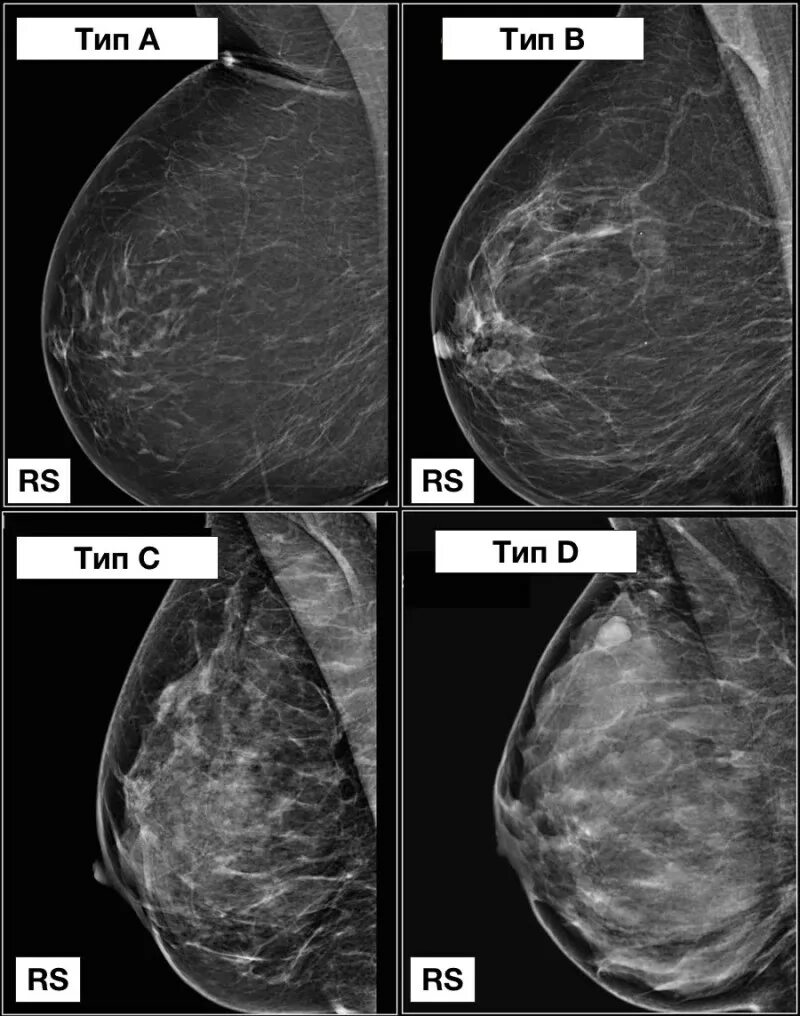

Acr тип b